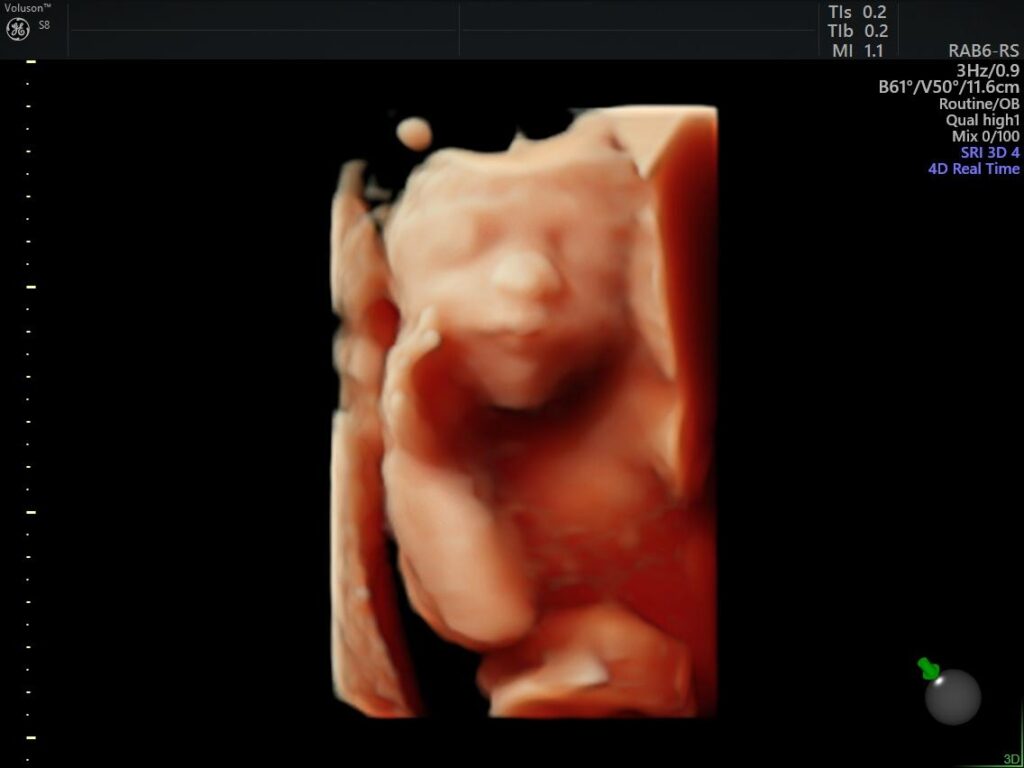

Ejemplos Ultrasonido: 4a Dimensión